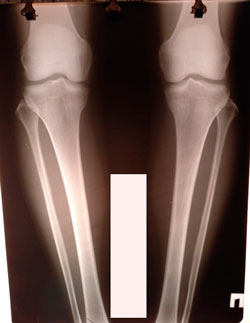

дата операции - 28.01.2021

дата снятия аппаратов - 17.06.2021

image-27-01-21-10-24.jpg

image-27-01-21-10-24-3.jpg